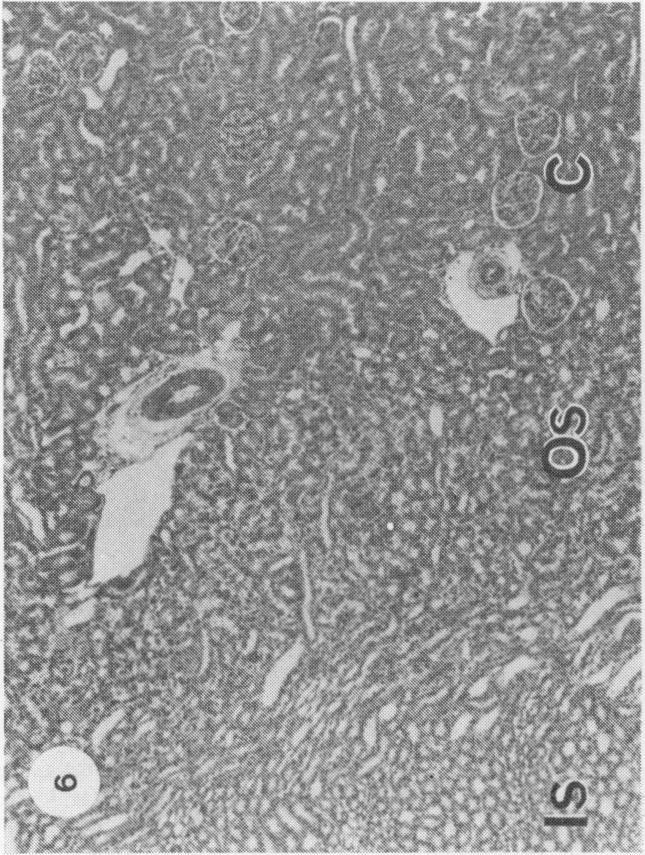

In JCLR and Wistar-Porton rats renal concentrations of Cd2+ were maximal (21-22 micrograms Cd2+/g wet wt tissue) at 1 and 4 h respectively after the administration of CdCl2 (10 micromol, 1-12 mg Cd2+/kg body wt) together with L-cysteine (5 mmol/kg body wt). Synthesis of metallothionein in the kidney in response to the uptake of Cd2+, which occurred between 2 and 7 h after treatment in the Wistar-Porton rat, affected the distribution of Cd2+ between proteins of the renal soluble fraction, but not between the particulate components and, at both times, about 40% of the total Cd2+ was associated with the heterogeneous nuclei + cell debris fraction. Autoradiographic studies with 109CdCl2 revealed that Cd2+, accumulated by the kidney under these conditions, was not uniformly distributed throughout the renal cortex, but was concentrated unevenly in proximal tubules in the outer stripe of the outer zone of the medulla. Pathological changes, which were correlated with the concentrations of accumulated Cd2+ and were limited to the S3 segments of the proximal tubules, were apparent by light microscopy at 4 h after the administration of Cd2+ + cysteine and progressed with time. Thus by 7 h the lesion had extended to include almost the whole of the outer stripe of the outer zone of the medulla and, by 24 h the cells of the affected epithelia showed extensive necrosis and karyorrhexis. At this, as at earlier times, the cortex appeared to be undamaged. Neither these nor other morphological changes were observed in the kidneys of animals that had been dosed with either Cd2+, or L-cysteine alone. Within 60 min of the administration of Cd2+ + cysteine an increase in the number of endocytotic vesicles in the apical cytoplasm of the proximal tubular epithelium was observed by electron microscopy. Subsequent cytoplasmic vesiculation, which was conspicuous at 2 h, was extensive and widespread in both the apical and basal regions of the cytoplasm at 4 h. In some cells at this time the nuclei were irregular in shape; the mitochondria were swollen and their cristae were disorganized. As, after the administration of either Cd2+ or cadmium-metallothionein, damage is known to occur in the S1 and S2 segments of proximal tubules throughout the cortex, the Cd2+ + cysteine combination does not provide an exact model which reproduces in a short time the effects of long-term, low level exposure to Cd2+. Nevertheless it is suggested that the toxic mechanisms are the same after either treatment with Cd2+ + cysteine or continual exposure to Cd2+, but are limited to different segments of the proximal tubules. Possible mechanisms of toxicity are discussed.

在JCLR大鼠和Wistar-Porton大鼠中,在给予氯化镉(10微摩尔,1-12毫克镉离子/千克体重)和L-半胱氨酸(5毫摩尔/千克体重)后,肾脏中镉离子的浓度分别在1小时和4小时达到最大值(21-22微克镉离子/克湿重组织)。在Wistar-Porton大鼠中,处理后2至7小时内,肾脏中因摄取镉离子而合成的金属硫蛋白影响了镉离子在肾脏可溶性部分蛋白质之间的分布,但不影响颗粒成分之间的分布,并且在这两个时间点,总镉离子的约40%与异质核+细胞碎片部分相关。用109氯化镉进行的放射自显影研究表明,在这些条件下肾脏积累的镉离子并非均匀分布于整个肾皮质,而是不均匀地集中在髓质外带外层的近端小管中。与积累的镉离子浓度相关且局限于近端小管S3段的病理变化,在给予镉离子+半胱氨酸后4小时通过光学显微镜可见,并随时间进展。因此,到7小时时,病变已扩展至几乎包括髓质外带外层的全部,到24小时时,受影响上皮细胞出现广泛坏死和核碎裂。此时,如同早期一样,皮质似乎未受损伤。单独给予镉离子或L-半胱氨酸的动物肾脏中未观察到这些或其他形态学变化。在给予镉离子+半胱氨酸后60分钟内,通过电子显微镜观察到近端小管上皮细胞顶端细胞质内吞小泡数量增加。随后的细胞质空泡化在2小时时明显,在4小时时在细胞质的顶端和基部区域广泛且普遍存在。此时在一些细胞中,细胞核形状不规则;线粒体肿胀且嵴紊乱。由于已知在给予镉离子或镉-金属硫蛋白后,整个皮质近端小管的S1和S2段会发生损伤,镉离子+半胱氨酸组合并不能提供一个能在短时间内重现长期低水平接触镉离子影响的精确模型。然而,有人认为,用镉离子+半胱氨酸处理或持续接触镉离子后的毒性机制相同,但局限于近端小管的不同段。文中讨论了可能的毒性机制。